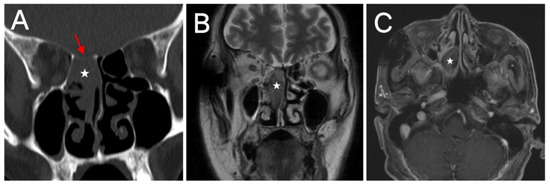

Objectives: We aimed to characterize the clinicopathologic features, treatment, and outcomes of three types of Switch/Sucrose Nonfermentable (SWI/SNF)-deficient sinonasal carcinomas (SDSCs), thereby expanding the spectrum of these rare entities and facilitating early diagnosis. Methods: We designed a retrospective single-center case series to analyze the clinicopathological features of 17 patients with SMARCB1-deficient sinonasal carcinoma (n = 10), SMARCA4-deficient carcinoma (n = 6) and SMARCA4-deficient sinonasal teratocarcinosarcoma (TCS) (n = 1) treated between 2018 and 2025, and reviewed the relevant literature. Results: The cohort included 14 males and 3 females, aged 26 to 69 years (mean, 47 years). SMARCB1-deficient sinonasal carcinomas predominantly involved the ethmoid sinus (6 of 8 patients), presenting epistaxis (7 of 10 patients), nasal obstruction (5 of 10 patients), and ocular symptoms (4 of 10 patients). SMARCA4-deficient sinonasal carcinomas mainly arose in the nasal cavity (3 of 4 patients), characterized by nasal obstruction (4 of 6 patients), and epistaxis or purulent rhinorrhea (4 of 6 patients); ocular symptoms were less common (2 of 6 patients). The TCS patient had left nasal cavity and ethmoid involvement with nasal obstruction and purulent rhinorrhea. Most patients presented with advanced-stage disease (T4a, n = 9), with skull base (n = 6), and orbital (n = 3) involvement. Histologically, immunohistochemical analysis confirmed complete SMARCB1 or SMARCA4 loss (complete in carcinomas and partial in TCS), diffuse CK positivity, and high Ki-67 indices. Treatment modalities included: chemotherapy and immunotherapy without surgery (n = 2), radical surgery with adjuvant chemoradiotherapy and immunotherapy (n = 2), radical surgery with chemoradiotherapy (n = 9), postoperative radiotherapy alone (n = 3), and non-radical surgery with chemoradiotherapy (n = 1). At a median follow-up of 19 months (range, 8–57 months), 2 patients were lost to follow-up, 3 died, 2 had persistent disease, and 10 remained disease-free. Conclusions: SDSC is an aggressive tumor with male predominance and advanced-stage presentation. Early recognition and appropriate immunohistochemical evaluation are essential for timely diagnosis and management. Prospective studies of novel targeted and immunotherapeutic strategies are warranted. Full article

Figure 1